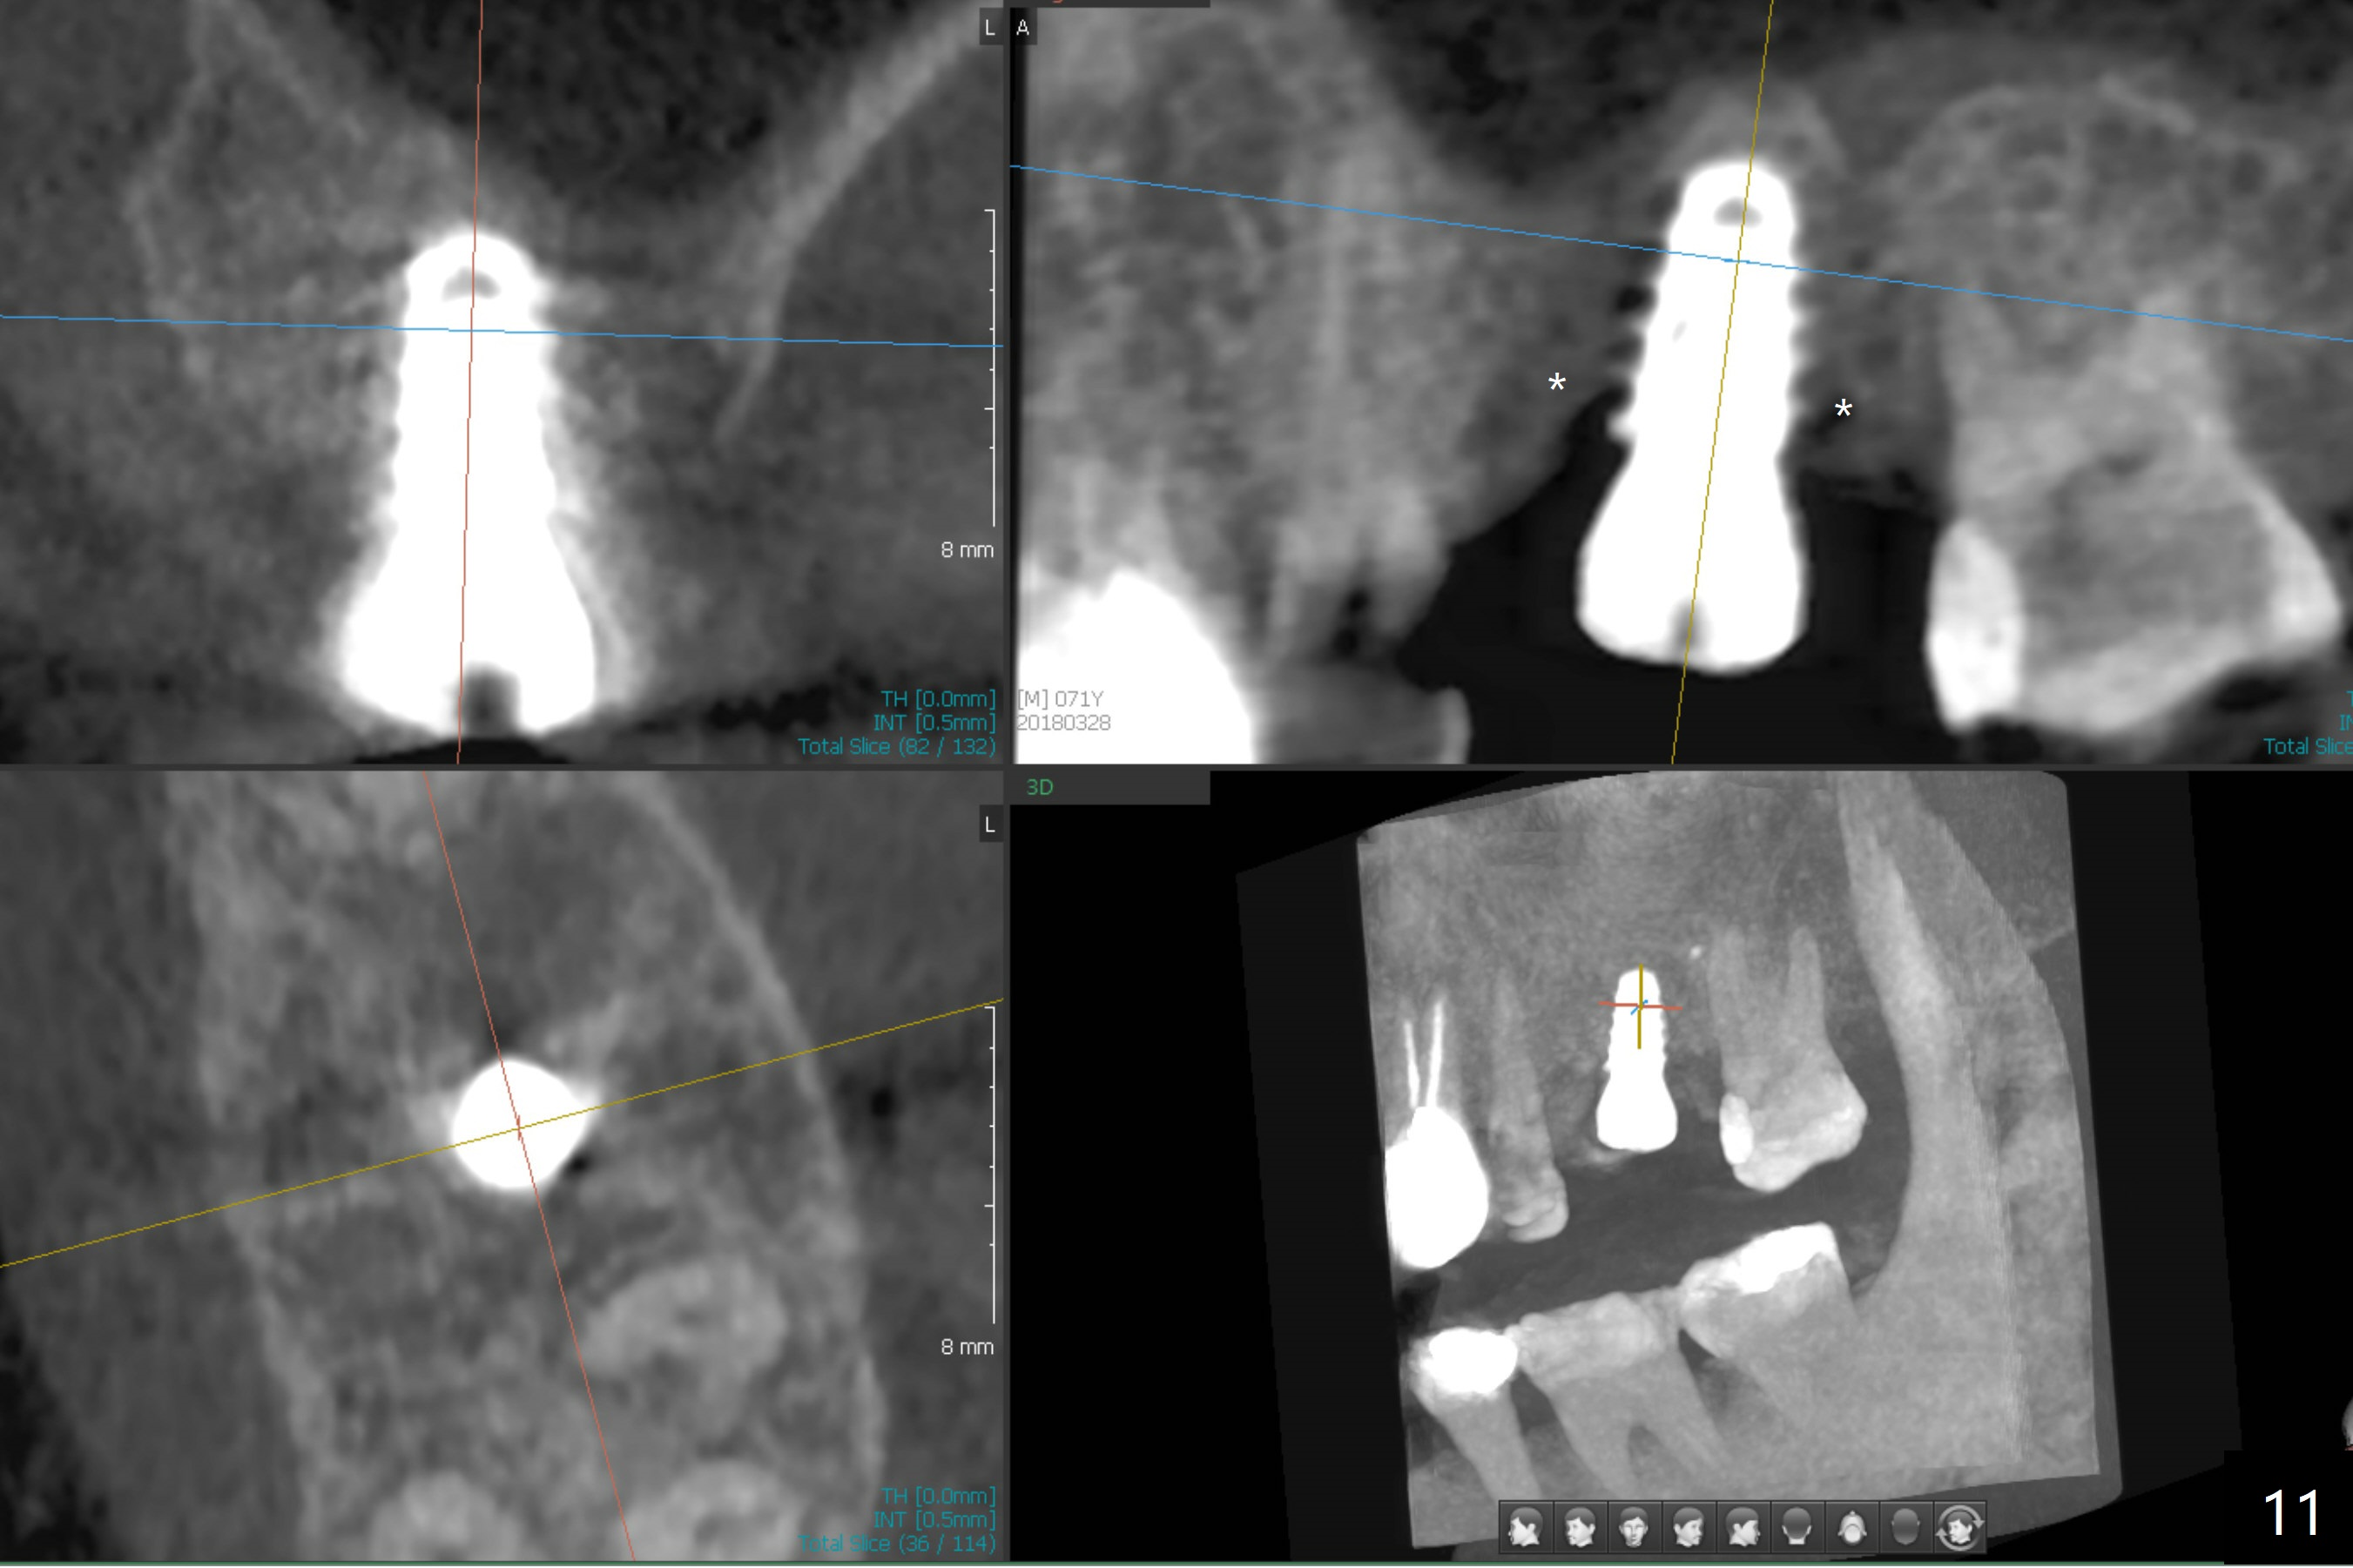

The implant is mobile 4 months postop (Fig.6). A 6x2 mm healing abutment is placed next. Although the implant remains mobile 6 months postop, the bone seems to have become denser around the implant (Fig.7-9). A healing screw is placed. When the bone height is limited (<7 mm), place a larger implant (>5.5 mm). The implant seems to have osteointegrated 8 months postop (Fig.10). Impression is taken following placing a 6.5x4(3) mm abutment. The patient reports pain after cementation, which is less when the abutment screw is loose (9.5 months postop, 2 weeks post cementation). CBCT taken after placement of a healing screw apparently shows loose bone mesial and distal to the implant (Fig.11 *). The implant trajectory is less favorable. It seems necessary to change to a large implant with more sold threads (Fig.12).